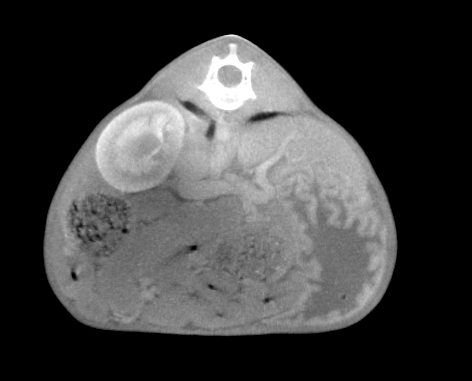

CT検査

シャント血管の発見にはCT検査が一番有効だと考えられます。血管の走行を立体的に把握し、問題点を明確に描出することが可能です。特に血管造影という方法を用いて、血液の流れを確認することで確定的な診断につながります。